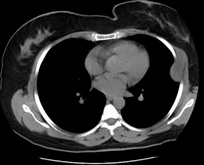

Figure 3b: Neurofibroma areas consisting of spindle-shaped and wavy nucleus cells and collagen (HEX400).